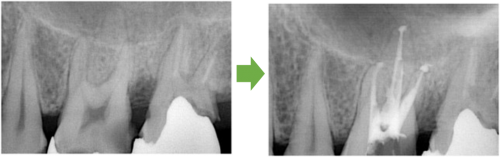

抜髄 左下の奥歯 川口の歯科 歯医者 さかえ歯科クリニック

2014年12月16日